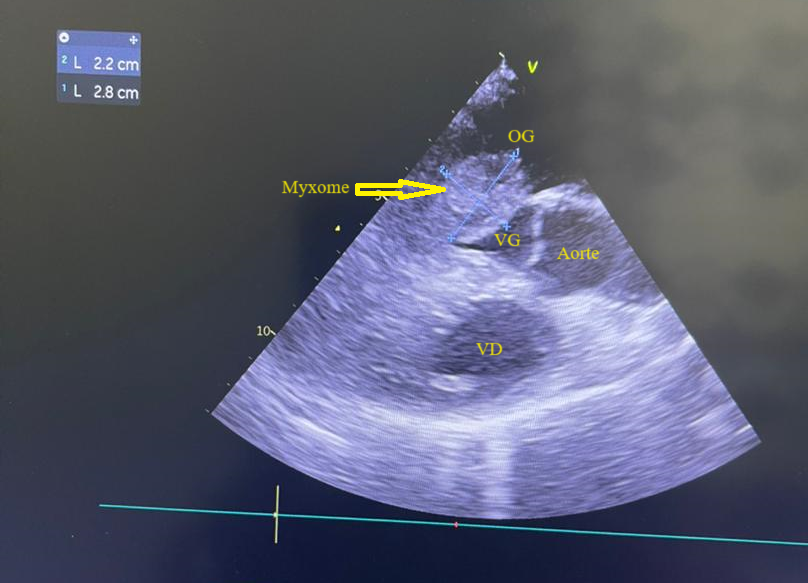

L’électrocardiogramme notait un rythme sinusal régulier avec une fréquence cardiaque à 83 bpm, des anomalies de la repolarisation en antéro septal à type d’ondes T biphasiques et en inférieur à type d’ondes T négatives asymétriques. La biologie était normale. L’échocardiographie (transthoracique et transœsophagienne) retrouvait les mêmes caractéristiques avec une masse appendue à la face atriale de la grande valve mitrale, obstruant partiellement l’orifice mitral et mesurant 49mm ×27 mm. Elle faisait protrusion dans le ventricule gauche en diastole (Figures 5 et 6). Cette masse était évocatrice d’un myxome de l’oreillette gauche. Le ventricule gauche n’était pas dilaté (DTDVG= 46mm), avec une fraction d’éjection systolique à 74% au Simpson biplan. Les pressions de remplissage du ventricule gauche étaient élevées. L’oreillette gauche était dilatée (VOG= 43mL/m²). Les cavités droites n’étaient pas dilatées. La fonction ventriculaire droite était normale (TAPSE= 24mm). On notait une hypertension pulmonaire avec PAPS =75mmHg, VmaxIT= 4,18 m/s. La veine cave inférieure était fine et compliante.

Figure 4 (a et b): Echocardiographie transoesophagienne en bi dimensionnelle, incidence 4 cavités plan oblique à 135° montrant un myxome appendu au septum inter atrial (Cas clinique n°2). VG= ventricule gauche ; OG= oreillette gauche ; VD= ventricule droit.

(a)

(b)

Figure 6: Echocardiographie transoesophagienne en bi dimensionnelle, incidence 4 cavités vue bi-commissurale montrant un myxome appendu à la face atriale de la grande valve mitrale et faisant protrusion dans le ventricule gauche en diastole (Cas clinique n°3). VG= ventricule gauche ; OG= oreillette gauche.